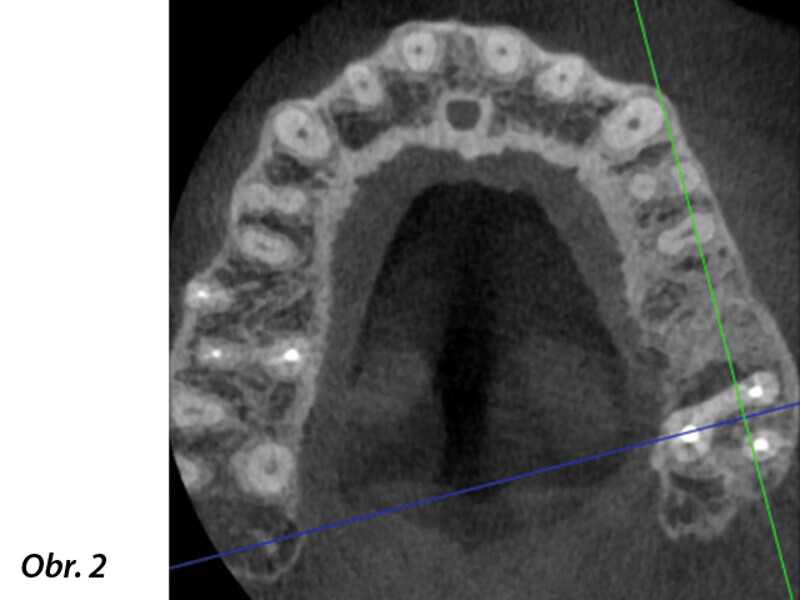

3D technologie v diagnostice a léčbě endodontických onemocnění